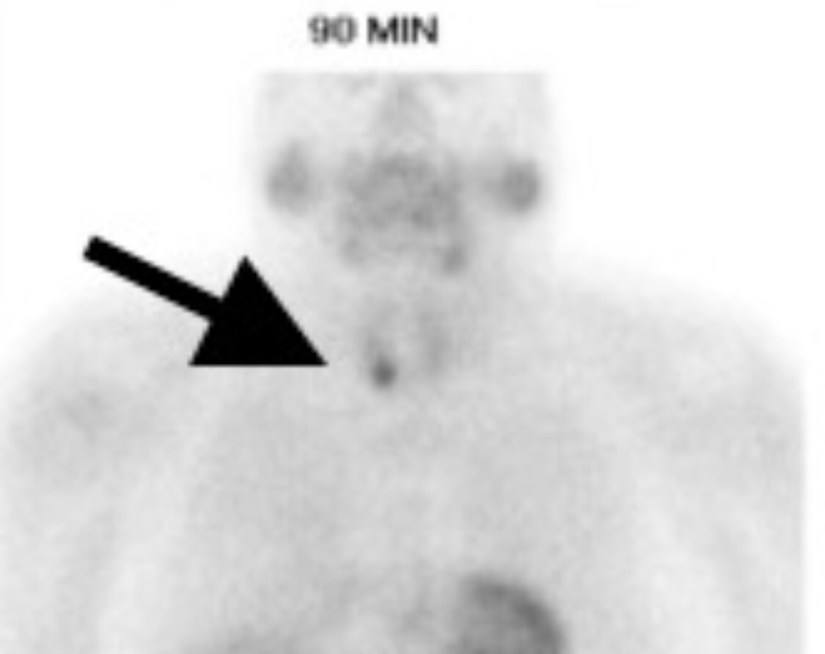

👉Patients with a negative Sestamibi scan are less likely to be referred to a surgeon (42.9 vs. 72.6% for a positive scan, e.g. below) even though a negative scan doesn’t preclude a curative parathyroidectomy.